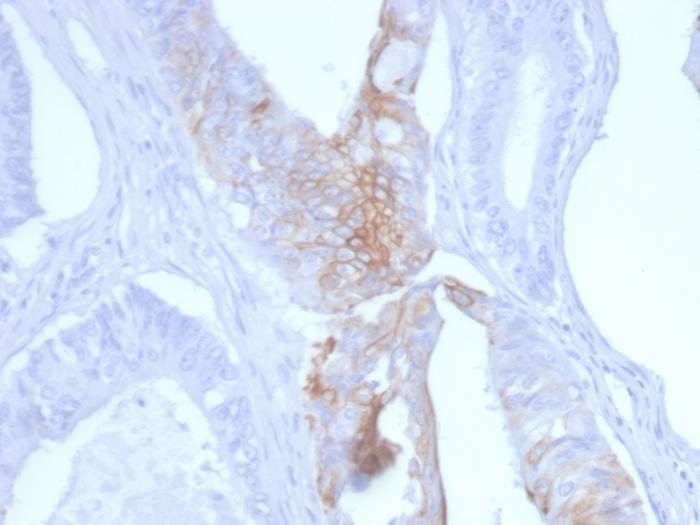

This MAb recognizes an intermediate filament protein of 46 kDa, identified as cytokeratin 20 (KRT20). KRT20 is abundantly expressed in goblet cells and enterocytes of the gastrointestinal tract. It is a useful marker of pancreatic and colorectal cancer. KRT20 is expressed under normal, hyperplastic and neoplastic conditions. It has been detected in adenocarcinomas of the colon, stomachand biliary tract. Breast carcinomas are generally non-reactive. Primary antibodies are available purified, or with a selection of fluorescent CF® Dyes and other labels. CF® Dyes offer exceptional brightness and photostability. Note: Conjugates of blue fluorescent dyes like CF®405S and CF®405M are not recommended for detecting low abundance targets, because blue dyes have lower fluorescence and can give higher non-specific background than other dye colors.

Positive Control

HT29 cells. Colon Carcinoma.